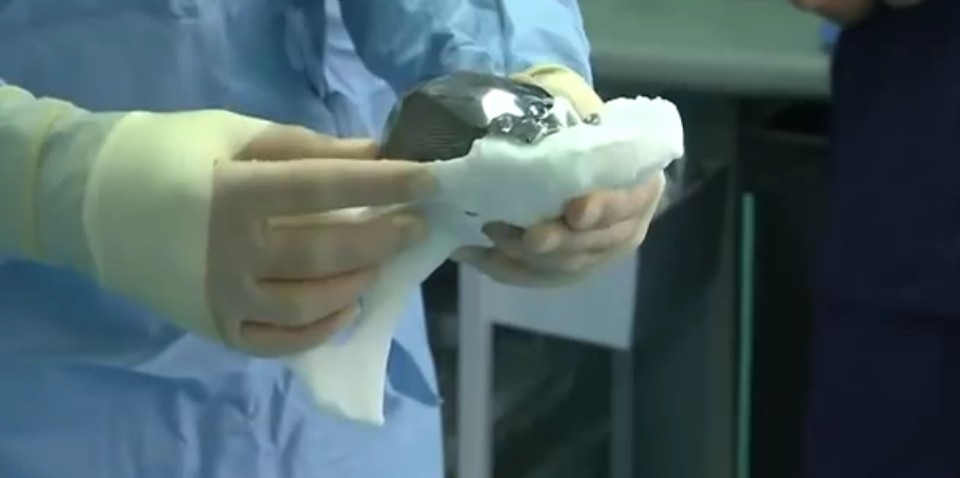

Patient Has 3D-printed Hip Replacement In Southampton - BBC News

www.bbc.com

www.bbc.com

China Food & Drug Administration Approves 3D Printed Hip Implants For

3dprint.com

3dprint.com

3d hip implants printed china 3dprint fda approves printing drug administration manufacturing additive use food medical

3D Printed Hip Implant Saves Woman From Pain And Disfigurement – Video

news.softpedia.com

news.softpedia.com

hip disfigurement implant saves